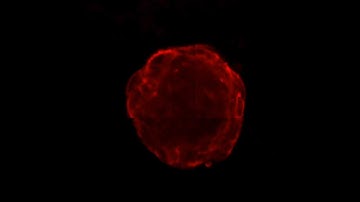

OpenLiver HepaRG NP 3D: MDR1 Labeling and Tissue Clearing